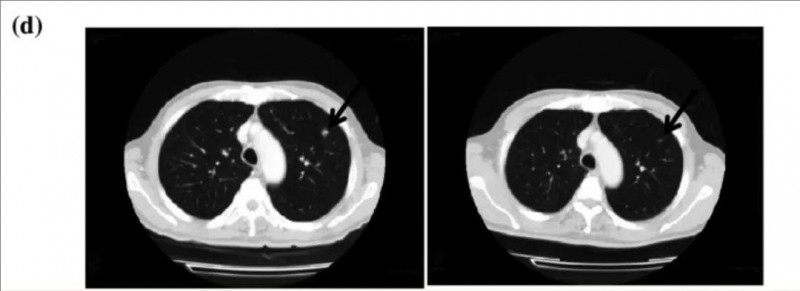

值得关注的是,患者TR05的转移性病变在γδT细胞治疗7个月内完全消失,且治疗完成后超过36个月仍保持无癌生存状态。治疗前后的CT影像对比显示,治疗开始3个月内,该患者的两处转移性病灶已在宏观层面消失(详见附图)。

▲图源“Cancer Immunol Immunother”,版权归原作者所有,如无意中侵犯了知识产权,请联系我们删除